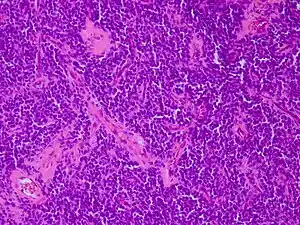

| Micrograph of an H&E stained section of a peripheral PNET. | |